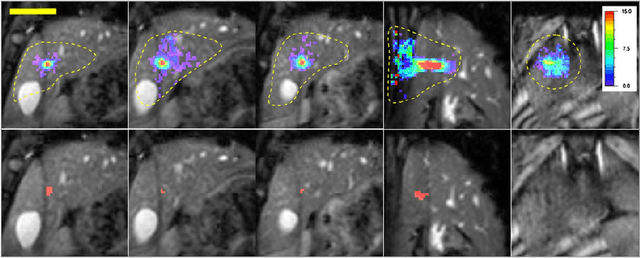

Abstract:High Intensity Focused Ultrasound (HIFU) can be used to achieve a local temperature increase deep inside the human body in a non-invasive way. MRI guidance of the procedure allows in situ target definition. In addition, MRI can be used to provide continuous temperature mapping during HIFU for spatial and temporal control of the heating procedure and prediction of the final lesion based on the received thermal dose. Temperature mapping of mobile organs as kidney and liver is challenging, as well as real-time processing methods for feedback control of the HIFU procedure. In this paper, recent technological advances are reviewed in MR temperature mapping of these organs, in motion compensation of the HIFU beam, in intercostal HIFU sonication, and in volumetric ablation and feedback control strategies. Recent pre-clinical studies have demonstrated the feasibility of each of these novel methods. The perspectives to translate those advances into the clinic are addressed. It can be concluded that MR guided HIFU for ablation in liver and kidney appears feasible but requires further work on integration of technologically advanced methods.